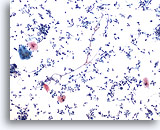

Grupos de actinomycetos contaminan de forma normal las muestras respiratorias. 60x

Lavado bronquial

Grupos de actinomycetos contaminan de forma normal las muestras respiratorias.

60x